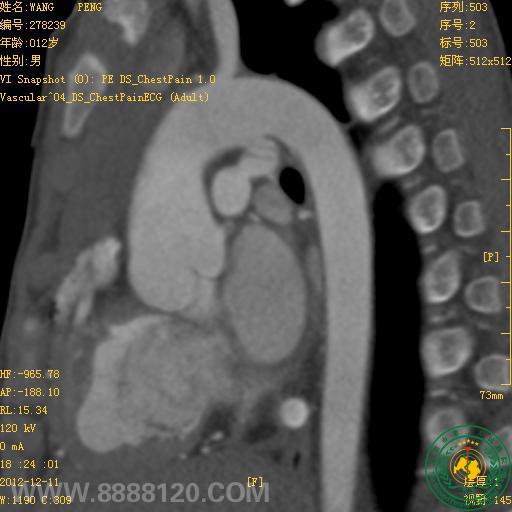

我院新双源CT在先天性心脏病中的首例应用

宜宾市第二人民医院 图文